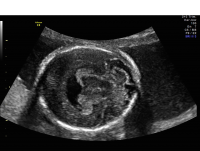

Holoprosencephaly

Holoprosencephaly is a severe abnormality in the development of the brain. In normal development, two sides of the brain develop. Holoprosencephaly is a condition in which the two sides of the brain do not separate normally. This condition occurs in approximately one in 8,000 second-trimester pregnancies.